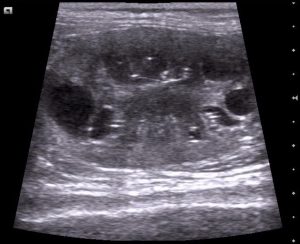

PKD ei ole tarttuva vaan geneettinen, perinnöllinen, varsin myöhään kehittyvä tauti. PKD muodostaa munuaisiin nestetäytteisiä rakkuloita (kystia), jotka valtaavat tilaa munuaisista ja aiheuttavat häiriötä kissan aineenvaihdunnassa (munuaisten tehtävä on muodostaa virtsaa ja poistaa sen mukana veren kuona-aineita). Munuaisten lisäksi kystia voi muodostua mm. maksaan ja kohtuun. PKD:n vaikutukset kissassa alkavat näkymään keskimäärin vasta noin seitsemän vuoden iässä. Oireina ovat mm. masennus, ruokahalun puute, pahoinvointi ja laihtuminen sekä lisääntynyt juomisen ja virtsaamisen tarve. Kissoihin erikoistuneen kanadalaisen eläinlääkärin Susan Littlen mukaan oireita kissalle alkaa syntyä vasta siinä vaiheessa, kun kystat ovat vallanneet suurimman osan munuaisten perustoiminnoista. Munuaisarvoissa PKD:n aiheuttamat muutokset alkavat näkymään vasta kun 2/3 osaa munuaisten perustoiminnoista on jo menetetty.

Yleisin diagnosointitapa on ollut ultraaminen vähintään 7,5MHz ultraäänianturia hyödyntäen. Kystia oletetaan olevan kissanpennulla jo sen syntymästä lähtien, mutta ne voivat olla liian pienet diagnosoitavaksi. Ihmisten PKD-tutkimuksissa on kuitenkin todettu, että kystat eivät välttämättä ole lapsella sen syntyessä vaan ne kehittyvät myöhemmin, joten kissojenkaan osalta tästä ei voida vielä olla täysin varmoja. 10 kuukauden ikäiseltä kissalta kystat pystytään erottamaan ultraamalla 95-98% todennäköisyydellä (ultraamisen sanotaan olevan maksimissaan 98% luotettava testausmuoto). Diagnoosiin vaikuttaa aina eläinlääkärin kokemus ja mielikuvat PKD:sta, laitteisto, kissan olotila (rauhoitettu vai rauhoittamaton) ja ultrataanko kissa kyljestä vai mahanpohjasta.